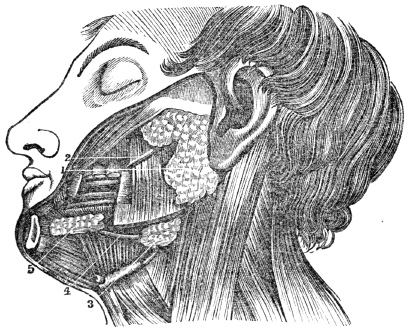

| 13. | Anatomy of the Digestive Organs, | 113 |

| 14. | Physiology of the Digestive Organs, | 124 |

| 15. | Hygiene of the Digestive Organs, | 129 |